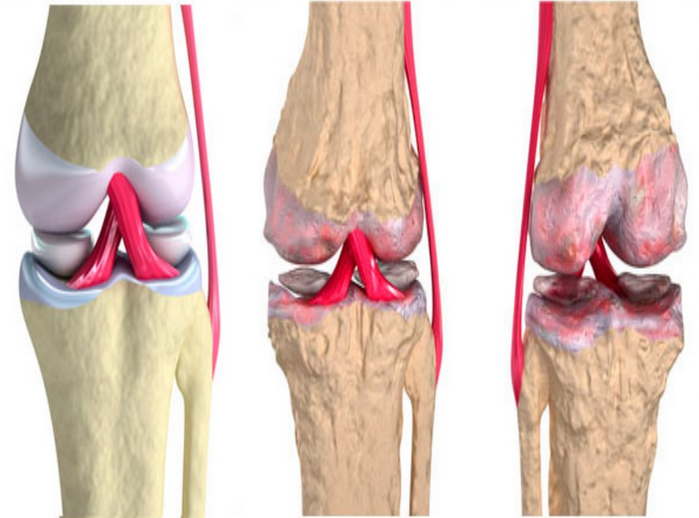

Медицинские состояния: Септический артрит коленного сустава